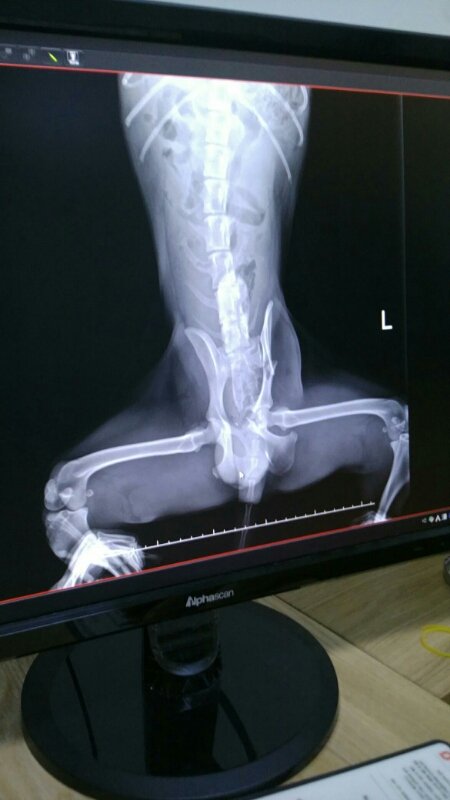

24시병원으로 옮겨 검진결과

앞두다리 골절과 골반 양쪽골절.

심장비대 신장기능이 멈춰 몸에 독소가 가득하답니다.

2~3일 지켜본후 수술여부를 결정한다고 하십니다.